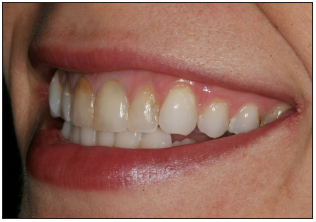

Front smile view

Show a full natural smile. Face should be relaxed. The vertical center of the slide should be the philtrum of the upper lip. Avoid compensating for midline discrepancies.

Confirm that the incisal plane of the maxillary teeth is the horizontal middle of the photo. If patient presents a canted incisal plane, duplicate position in this view. Camera should not be tilted to compensate for canted midline.

Stand directly in front of patient for straight on view. The camera should be 90 degrees to the patient's face. Teeth normally viewed in full natural smile should appear in image. Mandibular teeth may not appear.